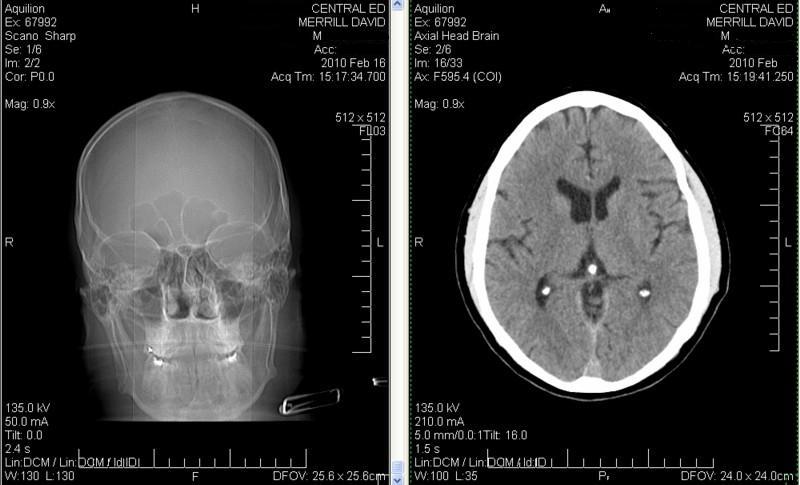

Load this CAT Scan of David Merrill's head by:

You will find two images in the left panel and 33 images in the right panel. Hold your mouse in either panel and scroll through the images

It looks to the layman me, like I have three pineal glands? After studying the links though, I think the other two calcified organs are my amygdali.

Click image for larger version

Name:	CAT Scan three stones sanitized.JPG

Views:	4

Size:	50.9 KB

ID:	46946

Posting the CAT Scan has been revealing for me. Decalcifying the amygduli too; they are associated with emotion and I am getting big on that "female" component in my thinking being in balance.

I crashed and cracked my head. I presume to watch the scan file like I show in the Opening Post you downloaded the entire file folder. There are pictures and audio files too about getting free emergency room care.